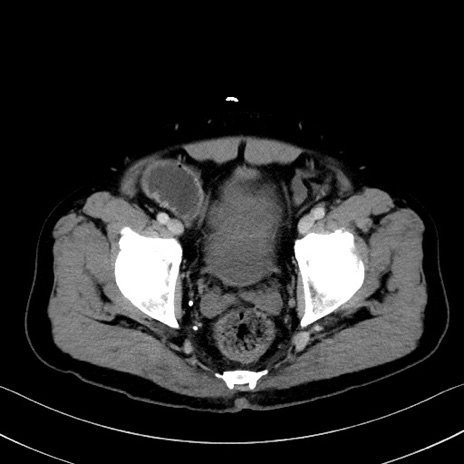

冠状断像

【症例】70歳代 男性

【主訴】腹部膨満、嘔吐

【現病歴】昨日より腹部膨満感出現。本日増悪し、仙痛出現。嘔吐あり、受診。

【既往歴】糖尿病、胆摘後

【身体所見】BP 149/80mmHg、HR 74/min、BT 35.9℃、腹部:膨満、軟、圧痛なし。腸雑音減弱あり。上腹部正中切開瘢痕あり。

【データ】WBC 13500、CRP 1.72